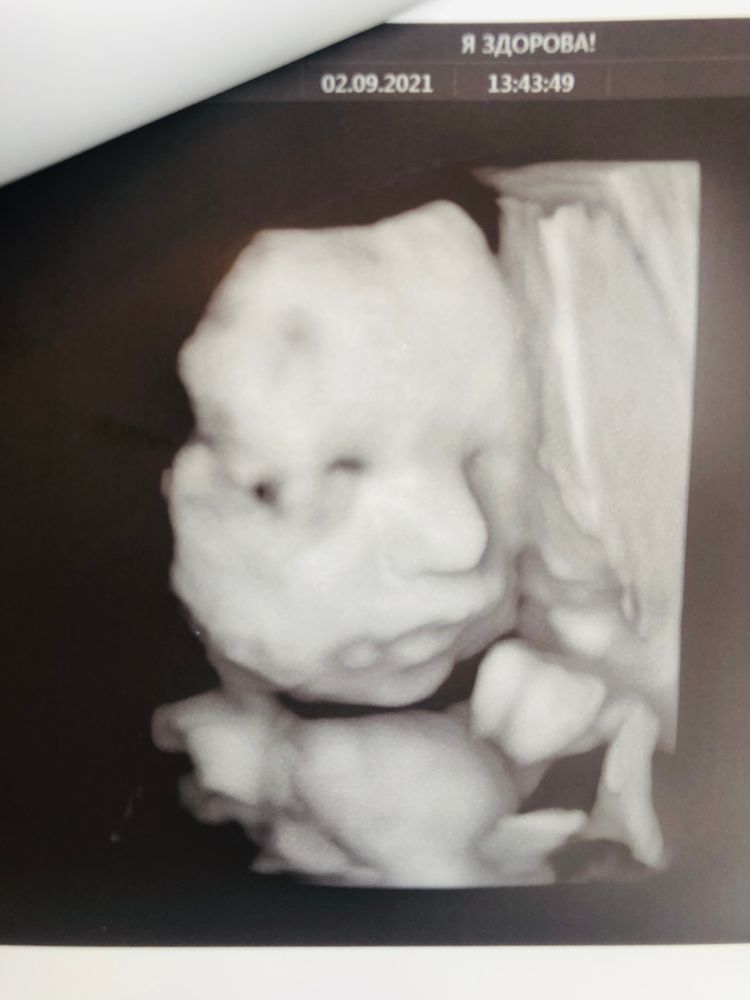

кто-то отказался видимо и я бегом-бегом и успела занять окно. Само узи длилось не долго, но очень информативно. Перед глазами у меня был экран. Я всё видела))))) периодически она переключала на 3д. Аппарат у неё мега крутой стоит. Врач всё померила, всё рассказала. Девочка наша мелкая, но всё соответствует. У меня все детки не крупные рождались. Воды норм, артерии лучше работают, когда я на боку лежу. Плацента 0 степени, шейка уже короткая. Головка, как я и чувствовала, очень низко, носить бандаж. Собралась уже на выход чтоли? Рановато ещё!!! Вес 1477+-200 гр. срок 30-31, животик и головка 29-30, мелкая девчушка)))) Нос папкин 😁, губешки мои☺️. Наталья Сергеевна сделала нам целый фотоальбом. За что ей огромная благодарность. Хотя 3 д, конечно, смешные фотки. Дети смеялись. Вообще она на Ваньку похожа очень😁